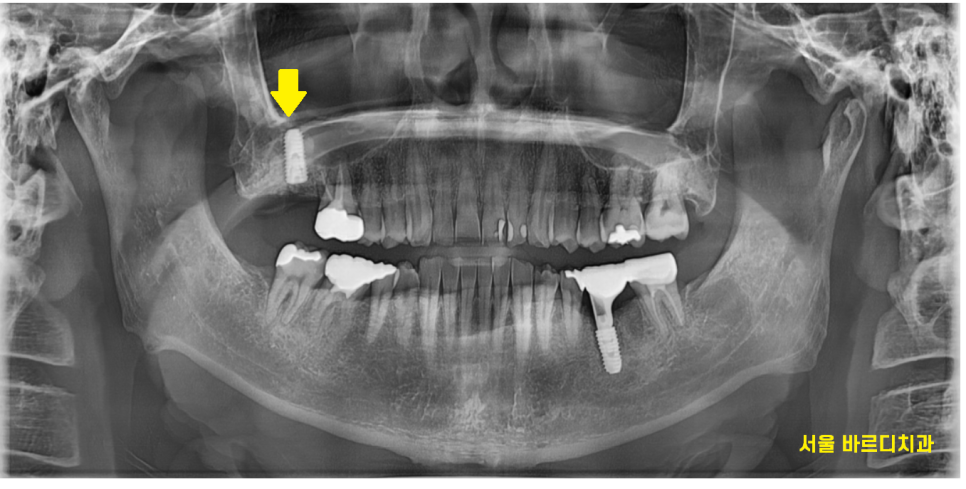

23.10.17

왼쪽 아래 임플란트를 치료중에

환자분께서 오른쪽 불편함을 호소하셨습니다.

처음 내원 시부터 치아가 흔들흔들 거리긴 했지만

잇몸이 안좋다 보니

잇몸치료 하면서 지켜보는 수밖에 없었습니다.

23.11.20

잇몸이 내려가 흔들거리긴 하였지만

강동구 임플란트 과정 중에

왼쪽이 치아 1개가 없어서

오른쪽 치아로 주로 씹다보니

더 불편하실 수 있다.

잇몸치료를 하며 최대한 살려보려고

노력했습니다.

24.01.16

왼쪽 아래 강동구 임플란트 치료중

계속하여 경과관찰을 하였는데요.

ct속 문제의 치아

뼈가 내려가다못하여

뿌리 염증까지 심해져서

이제 시기가 되었습니다.

놓아줄 시기가 되었다는 뜻이죠ㅠㅠ